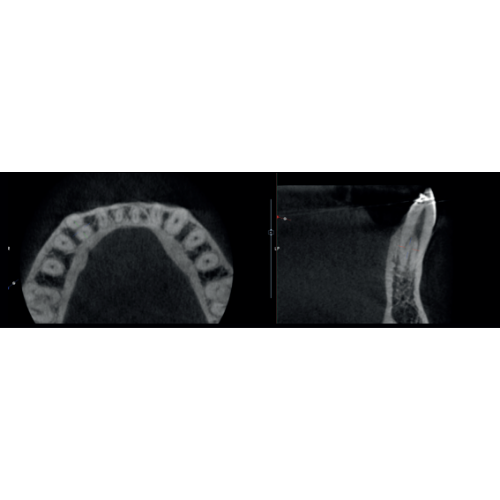

X-MIND® optima 3D represents the perfect combination of advanced hardware technology, enclosed in a lightweight and compact design and next-generation software, RealGuide™ 5.4, bringing the benefits of Artificial Intelligence into every step of patient care, from a precise diagnosis to more effective treatments and patient communication.

- Field Of View: 5x5, 8.5x5, 8.5x9, 12x10

- Focused FOV